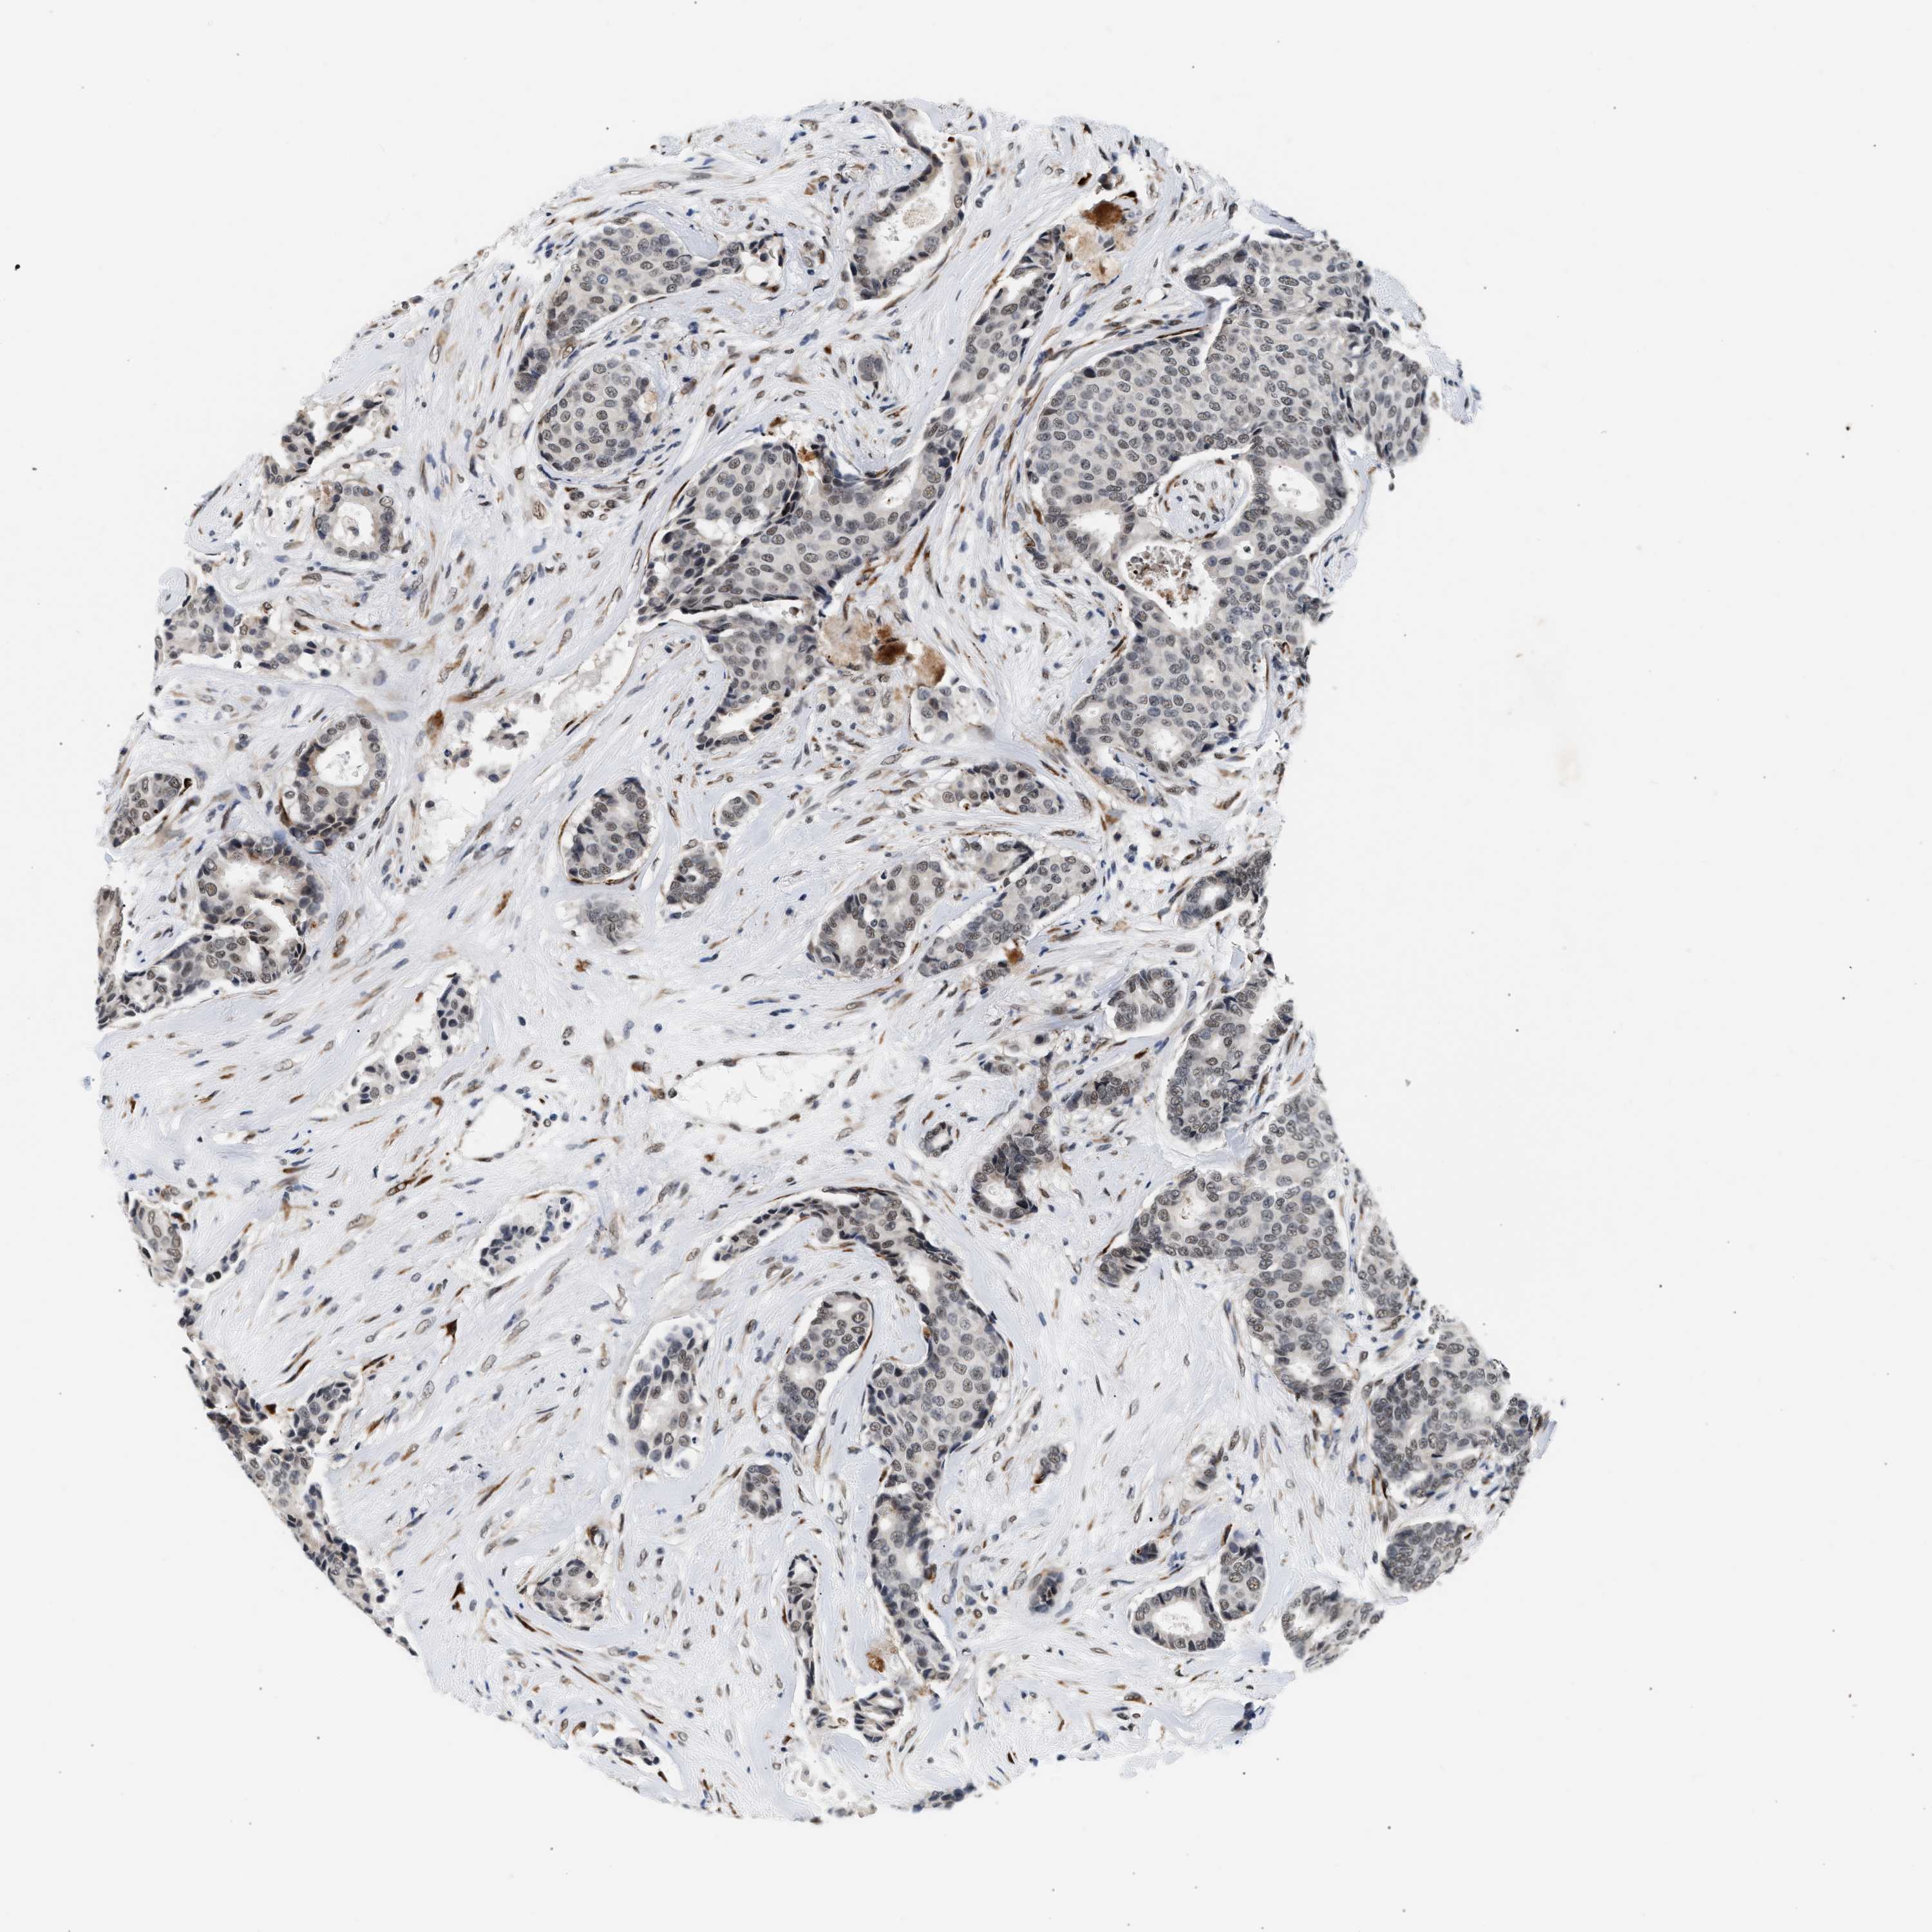

CANCER BREAST CANCER Show tissue menu

BRCA TCGA BRCA VALIDATION PROTEIN EXPRESSION